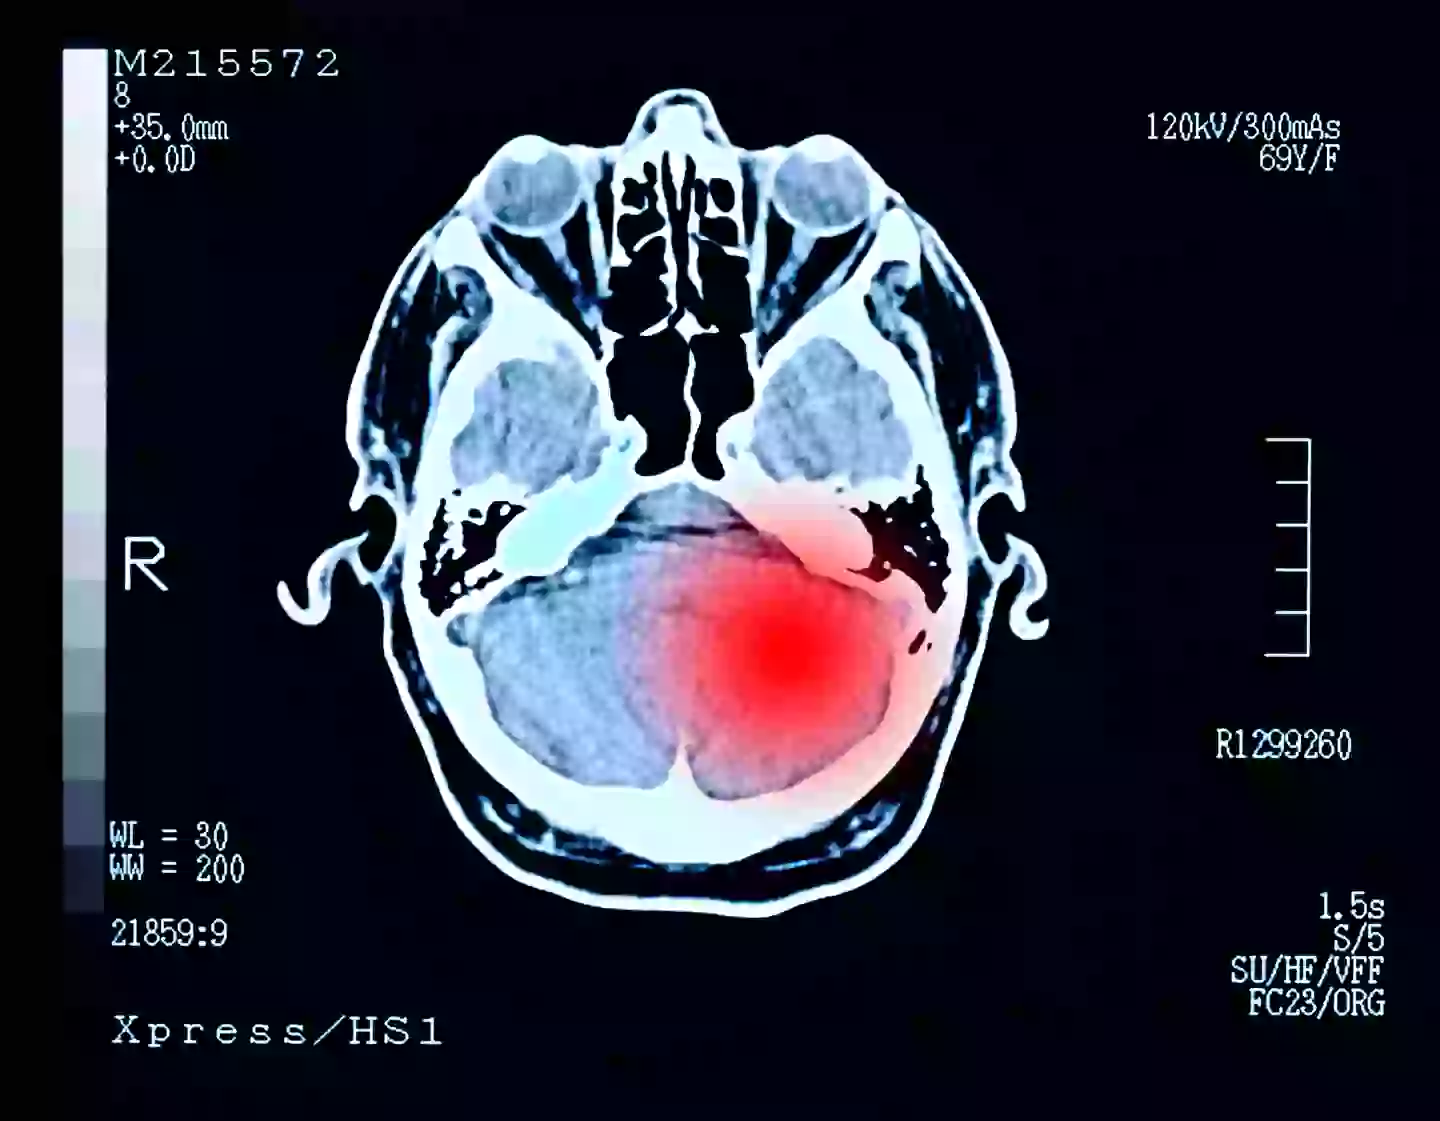

The symptoms of a benign brain tumour can be ‘subtle’. (Getty Stock Images)

Walsh was told she had a ‘very sizeable brain tumour’ in her ‘left frontal lobe’, leaving her lost for words.

Thankfully, the tumour was benign, meaning that it was non-cancerous.

Benign brain tumours can have slightly different symptoms to cancerous ones, according to the NHS.